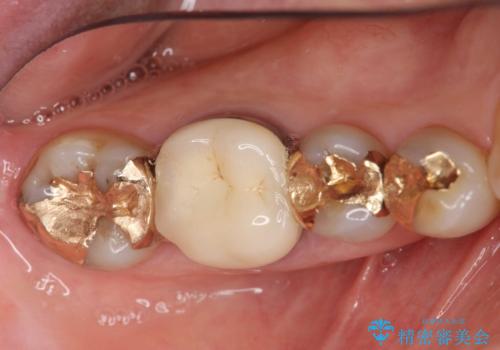

- 笑った時に目立つゴールド修復を、白く自然なセラミック治療に置き換えたいとセラミック治療を希望され来院されました。

X線検査により、ゴールド修復下に虫歯の再発を多数認めました。

ゴールドの除去後に虫歯を丁寧に除去、セラミックにて自然な美しさを回復できるよう治療を計画します。

- 34.1万円(ジルコニアクラウン×2・仮歯×2・セラミックインレー×1)費用は治療当時の料金となります